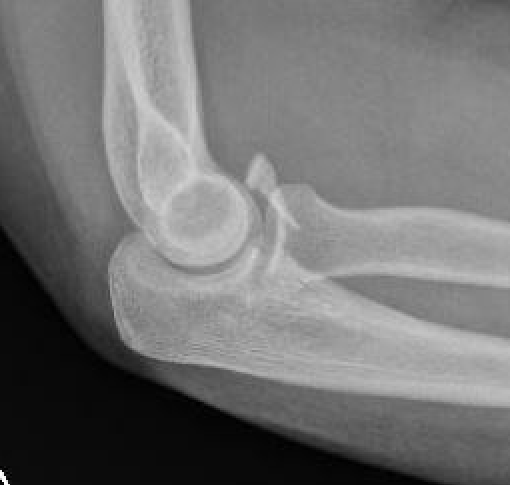

Coronoid Fracture Type 1 coronoid Type 3 Coronoid Fracture

Regan and Morrey classification of transverse coronoid fractures

Elbow stability related to size of coronoid fragment

Small coronoid process fracture 50% of coronoid process > 50% coronoid process

Usually stable

Elbow unstable